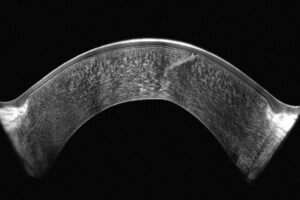

2. Voordelen van de Cornea-OCT-technologie

Hoge-resolutie OCT-technologie maakt gedetailleerde visualisatie van de corneale structuren mogelijk, inclusief nauwkeurige meting van de epitheliale dikte. Deze meting is cruciaal voor de vroege detectie van corneale ectasie. Epitheliale diktemapping ondersteunt bovendien de chirurgische planning, wat bijdraagt aan optimale resultaten van refractiechirurgie. OCT-beeldvorming is bovendien essentieel voor:

- Ultra hoge resolutie over het gehele hoornvlies

- Uniek groothoek pericentrisch scansysteem